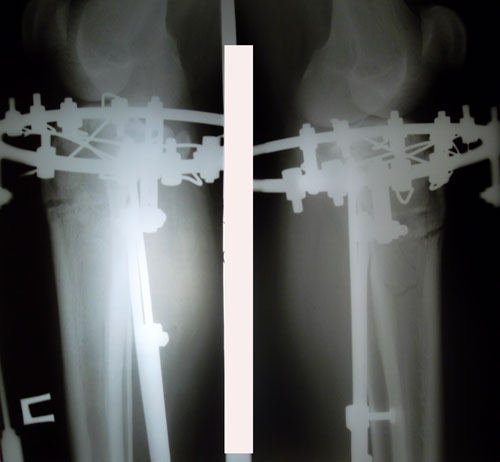

Исходник - 23 года.

Дата операции 23.03.2016г.

Дата снятия аппаратов 22.06.2016г.

Срок лечения 89 дней.

P.S. пациент сросся за 74 дня. По желанию клиента, мы перехаживали.